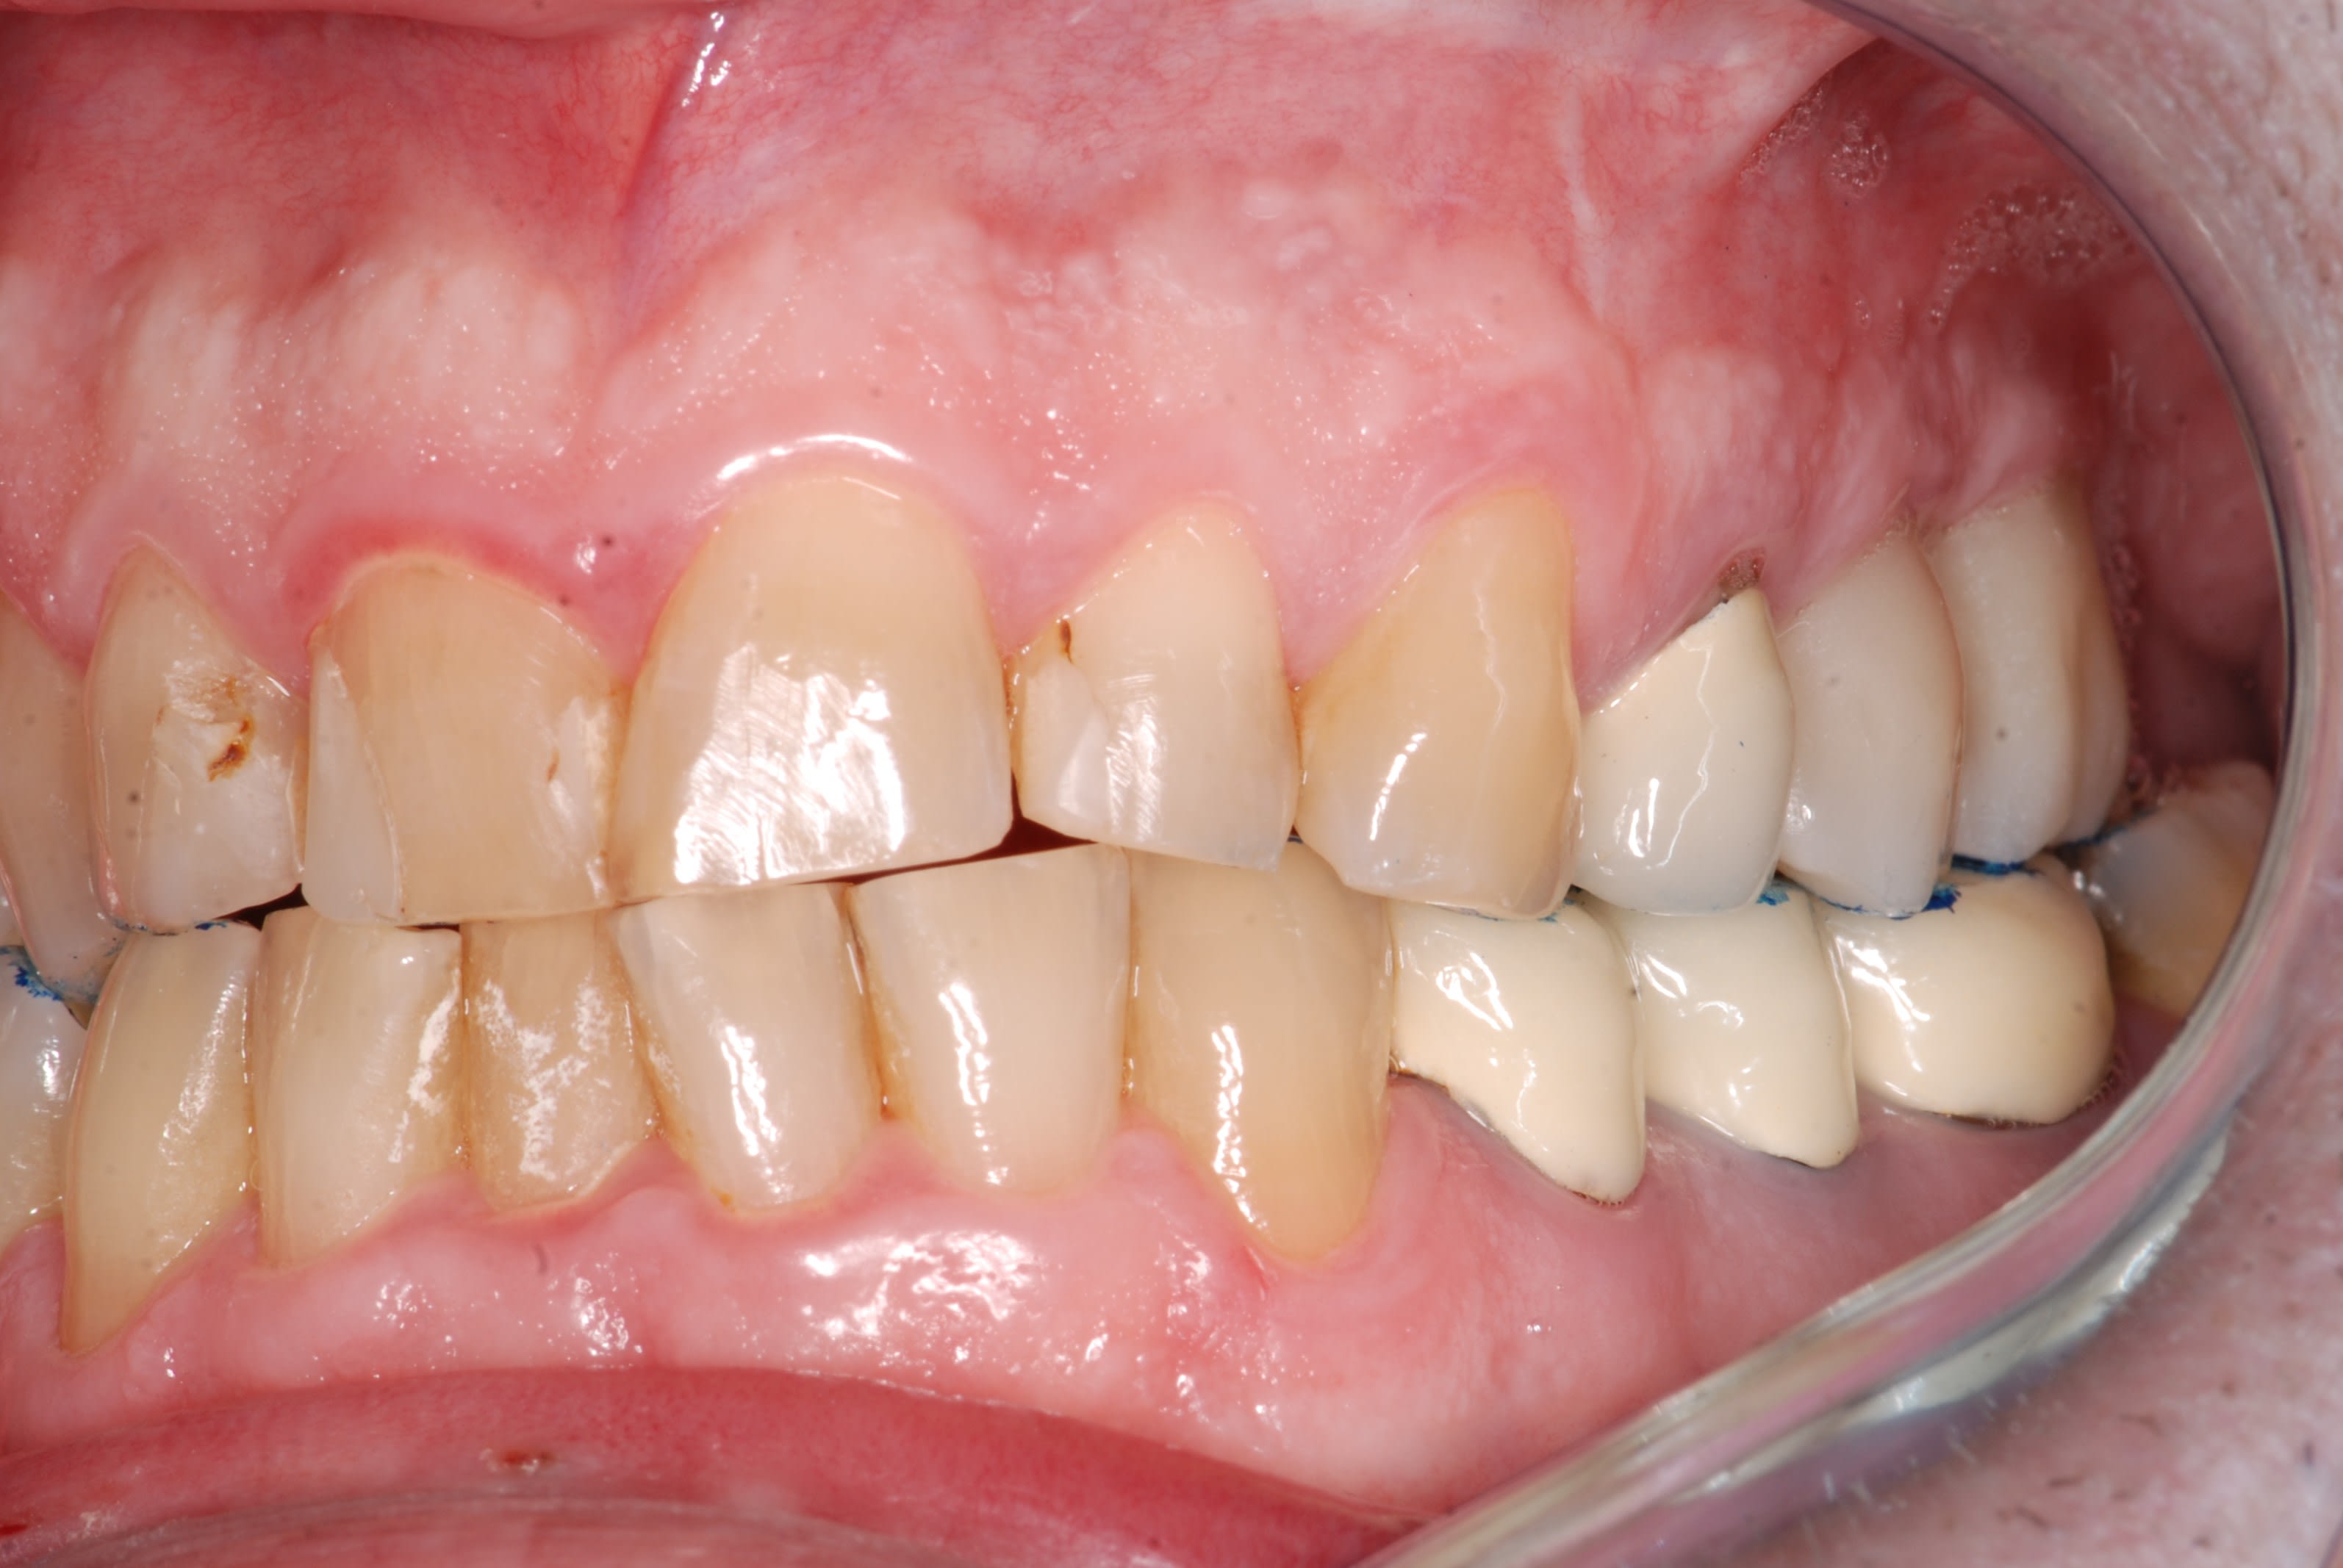

Ce patient vient me voir pour une dent "qui est remontée dans sa gencive" associé à des douleurs à la mastication

Effectivement en bouche la 16 est complètement ingressée.

Comme promis, voici les photos du cas.

Comme je disais on dirait que la dent est remontée avec tout son parodonte...

Rien de particulier de noté au cbct fait par mon correspondant implanto. je vais lui demander les coupes